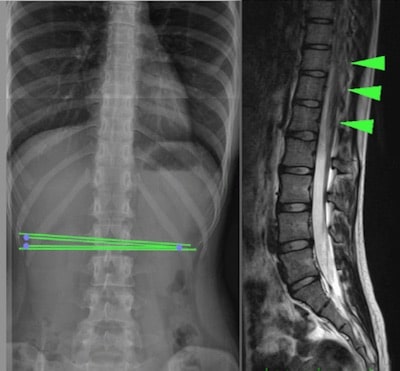

A medula presa oculta ou “Occult Tethered Cord Syndrome” está relacionada a uma espinha bífida oculta, uma malformação neuro-espinhal, que consiste no desenvolvimento incompleto da medula espinhal (principalmente na região lombar), que fixa a medula espinhal e produz lesões mecânicas por tração, principalmente medulares e vertebrais (Fig.1).

Para se visualizar e fazer este diagnóstico, são necessários exames complementares, tais como a Ressonância Magnética, a Tomografia Computadorizada ou ainda uma radiografia simples da região da coluna vertebral onde se encontra o ancoramento.